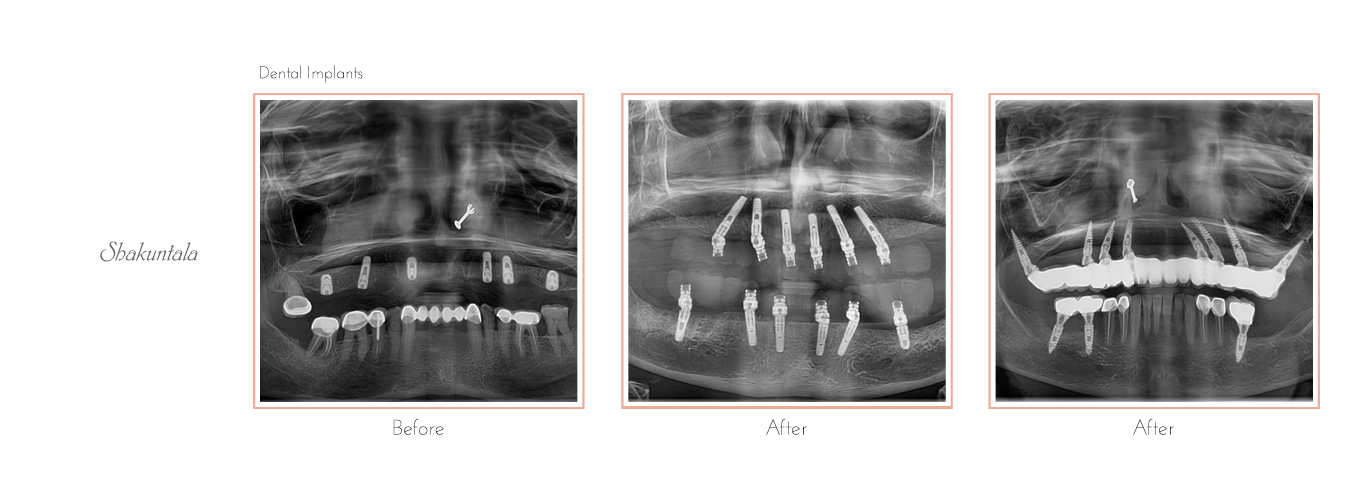

Dental Implants

Dental Implant Procedure

Placing a dental implant has various stages.

Healing

• During this process, the jawbone will grow and unite with the surface of the dental Implant. This process is also called osseointegration, as it helps to offer a durable base for the new artificial tooth, much like roots do for the natural teeth.

• Generally, this process takes 3 to 6 months, depending on the bone health & structure.

• After that, you can schedule the second surgery, but only once the implants are fused with the bone. Your dentists will take an x-ray to confirm whether the Implant is fit for the second surgery.